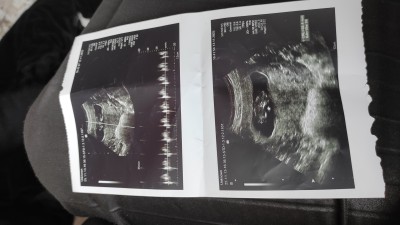

imagebanada yorum yapın

Kiz canim cikintiisi altta ikinci resimde

Kız bebek olacak görünüyor sağlıkla gelsin ♥️